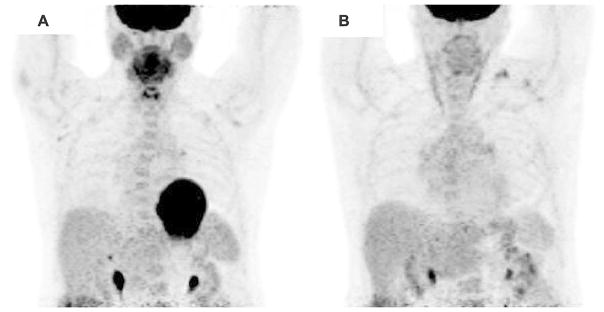

Figure 3.

Cardiac 18F-FDG PET imaging of a patient with suspected cardiac sarcoidosis with A poor myocardial suppression following non-compliance with 4 hour fast prior to 18F-FDG imaging and B excellent suppression following appropriate dietary preparation and fasting demonstrating no focal 18F-FDG uptake.